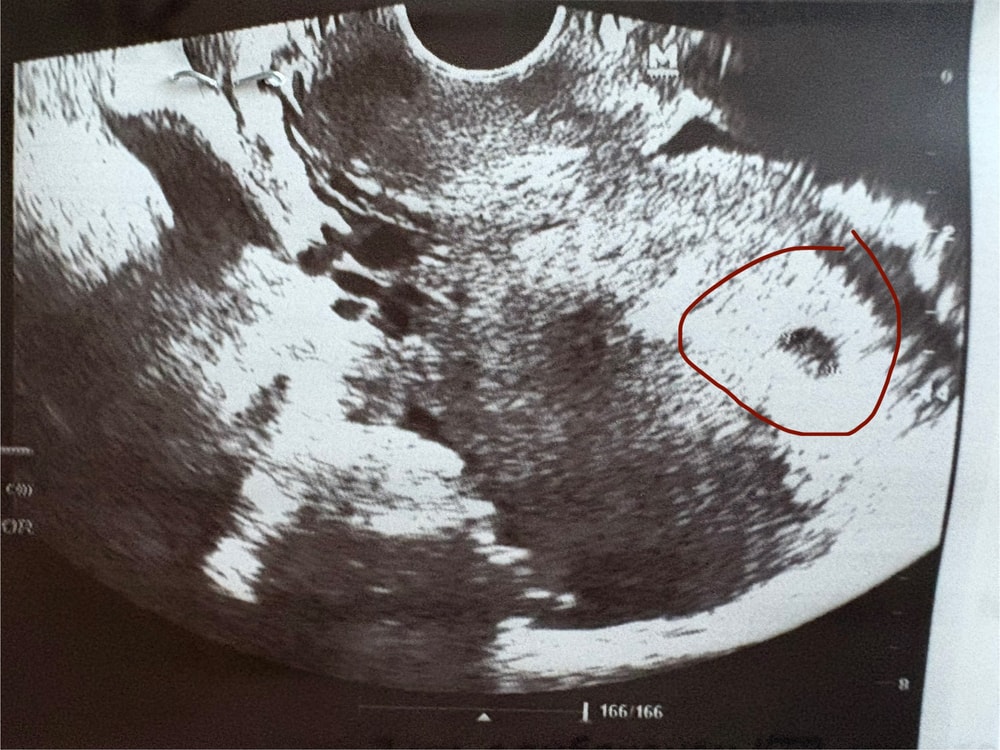

5 акушерских недель 🥰

Узи 10 недель пришел мой второй ХГЧ на 18ДПО 1872🥹